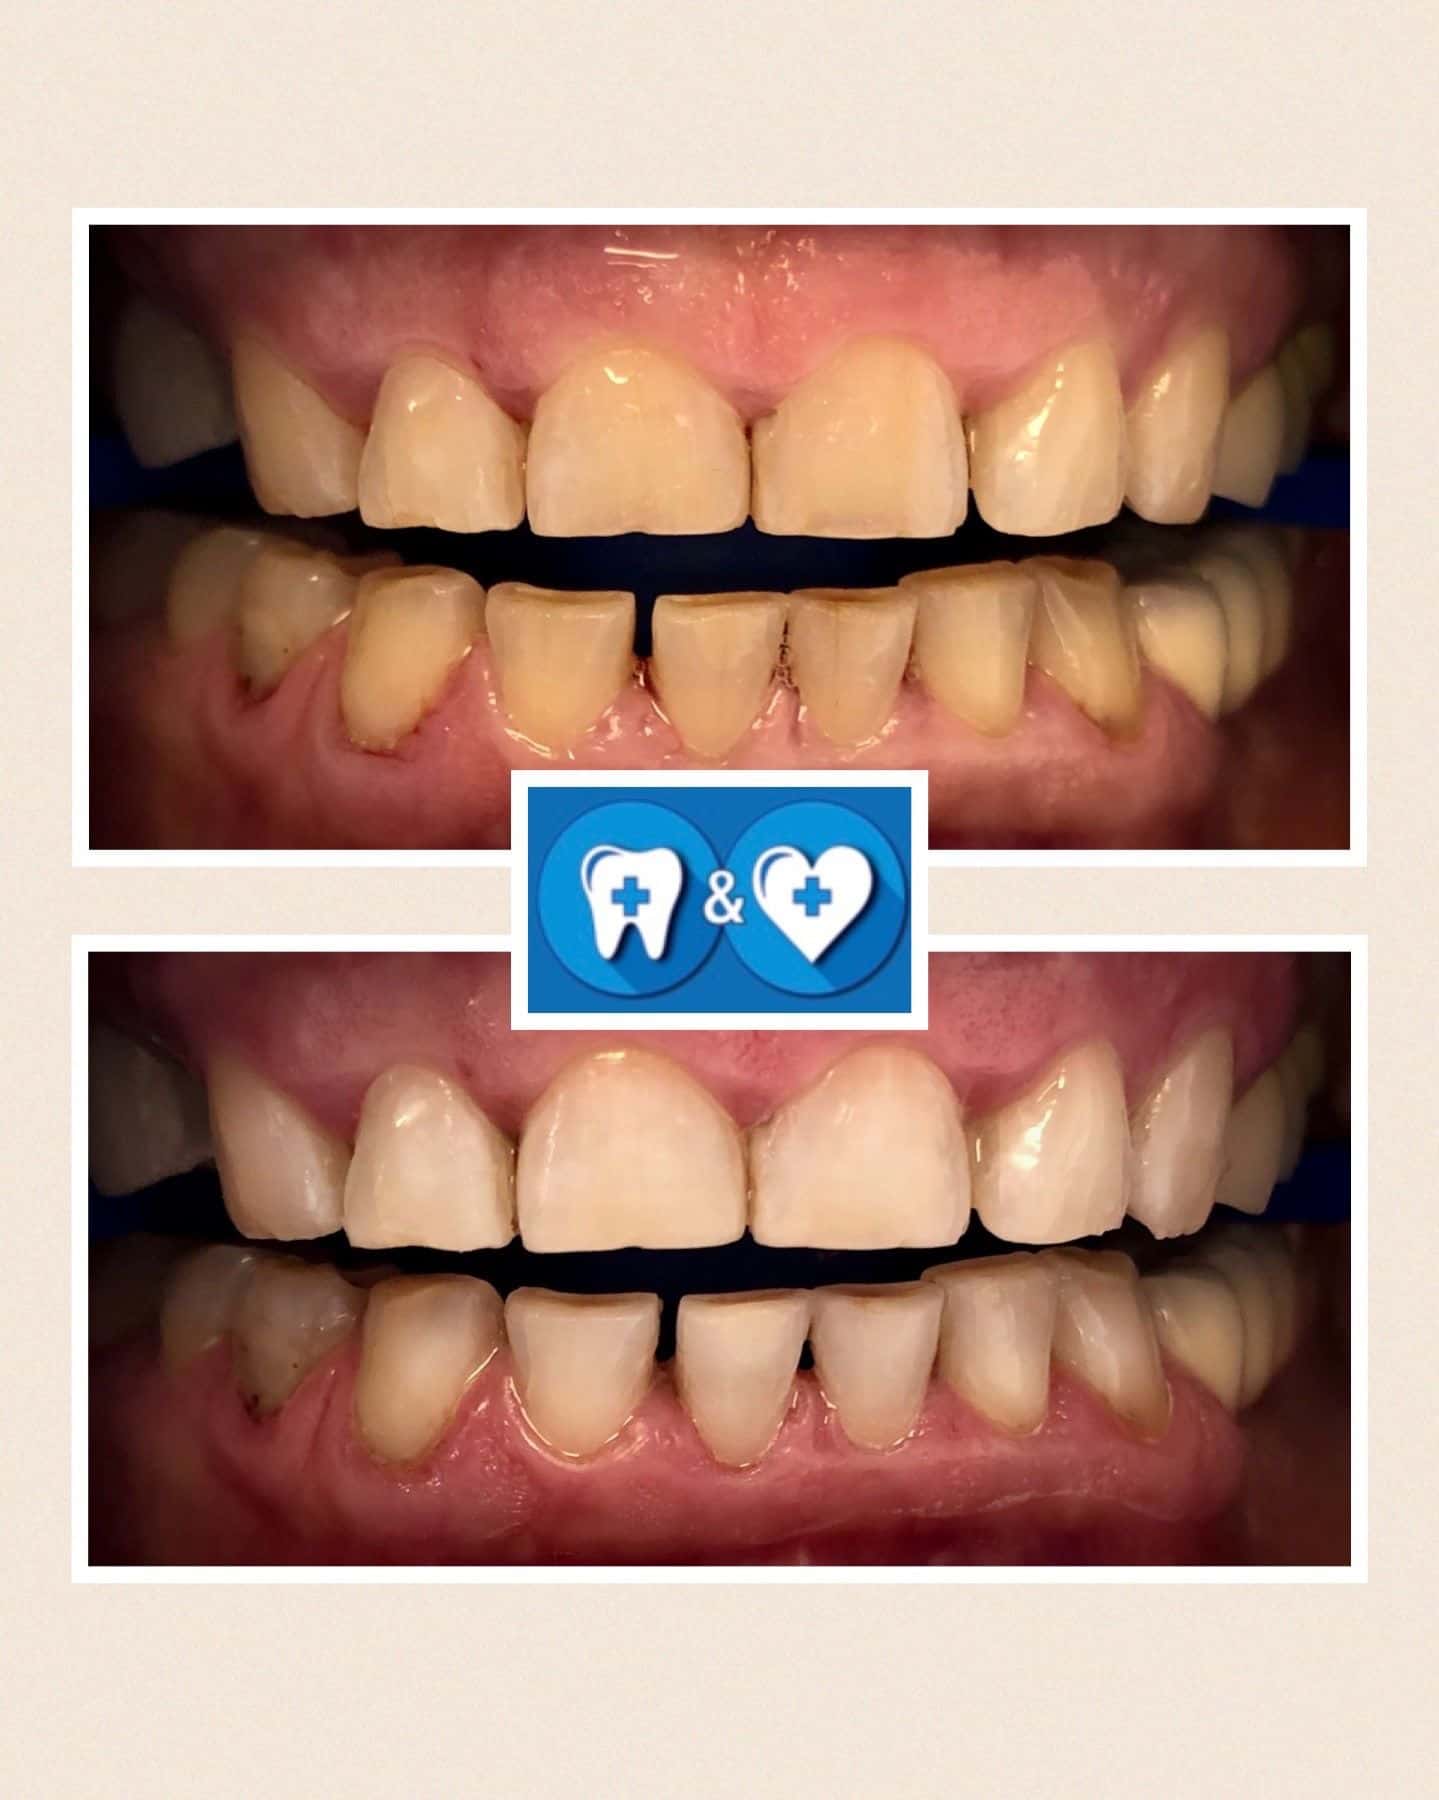

Specialiais instrumentais ir ultragarsiniu skaleriu pašaliname ant dantų susikaupusius akmenis. Su smėliasrove ir perlų soda nuvalome tabako, arbatos, kavos, vyno apnašas.

Dantų poliravimas su soda, E-FLOW technologija leidžia pašalinti atsiradusias pigmentines dėmes!

Po burnos higienos procedūros dantys bus daug gražesni ir baltesni! Ir sveikesni!